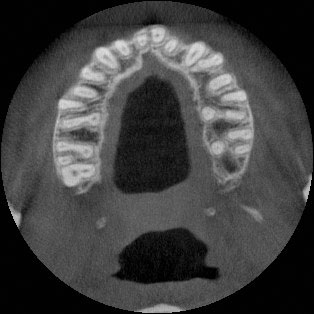

A 27-year-old female patient presented with class III malocclusion, 15 mm crowding in the upper arch, an anterior open bite, a lateral crossbite, and a total ABO score of 29. Her facial profile was straight with a retrusive maxilla, and the upper and lower incisors were retroclined. An extreme lack of midface support was also noted, and the constricted dental arches resulted in a poor smile width and dark buccal corridors. No myofunctional investigations were performed at the time, as they were initially considered unnecessary.

The treatment began in 2017. Given the patient’s preference for less visible brackets, Damon Clear brackets were selected. High torque upper cuspids and low torque upper incisors were chosen to offer the best torque control for upper arch development. For the lower arch, there were no alternative bracket configurations available. Bite turbos were applied to the upper second molars.